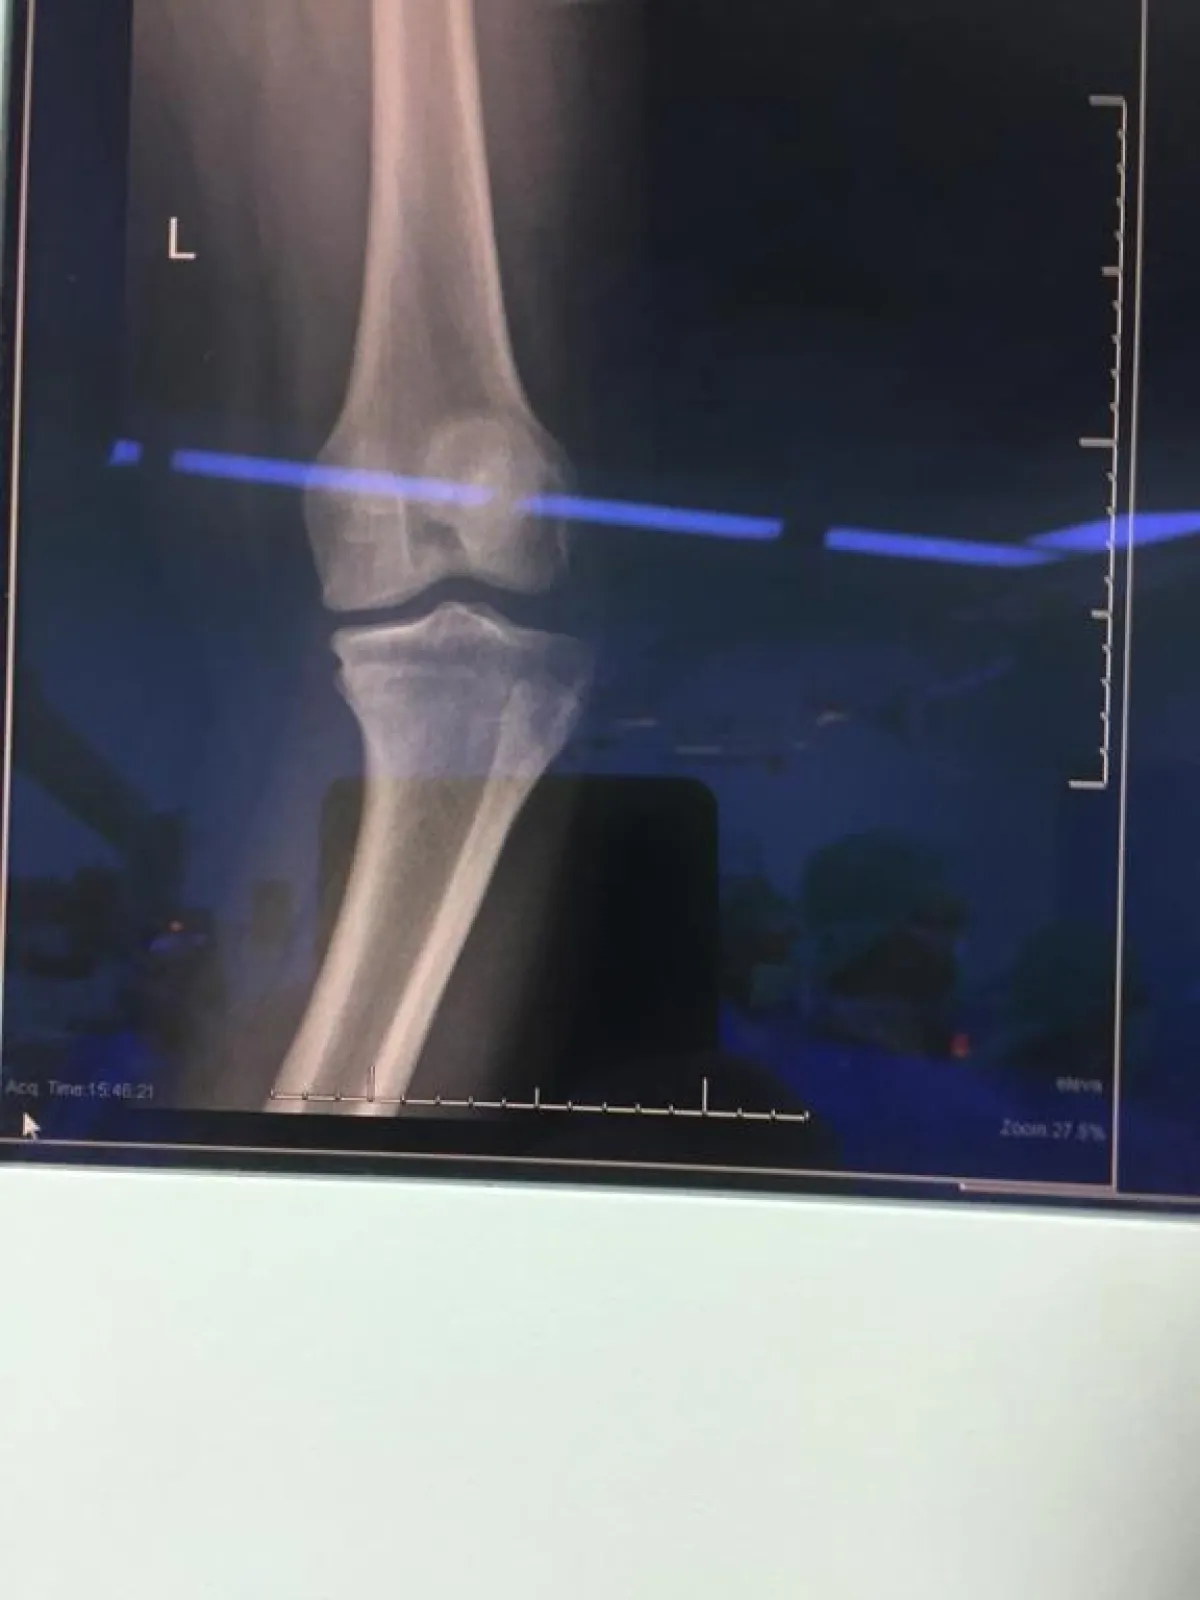

نجح قسم العظام في مستشفى الملك عبد العزيز بجدة من إجراء جراحة ناجحة لشاب في العقد الثاني من العمر يعاني من تقوس بارز في عظام الساق، و تطلب ذلك اجراء عملية واحدة خلاف العمليات المألوفة، و التي تعتمد على التعديل التدريجي بواسطة جهاز تثبيت خارجي يبقى ملازم للمريض لمدة لا تقل عن ستة أشهر .

و أوضح استشاري جراحة العظام بمستشفى الملك عبد العزيز بجدة الدكتور محمود الصالحي أن الشاب تمكن من استعادة استقامة ساقية بعد استخدام جهاز التثبيت الخارجي، حيث كان يراجع العيادة الخارجية بسبب معاناته من تقوس الساقين، و بعد إجراء الفحوصات الطبية الدقيقة والإشعاعية و المخبرية اللازمة، لنبدأ بعدها الخطة العلاجية من خلال تقنية تثبيت الجهاز الخارجي، مبيناً أن الطريقة التقليدية لعلاج مثل تلك الحالات تتم عبر التدخل الجراحي لوقف نمو صفائح النمو في الجهة التي يحدث بها التقوس بشكل يدوي ، و لكنها قد لا تنجح في كل الحالات و قد يستمر التقوس أكثر، مؤكداً استعادة الشاب لممارسة حياته الطبيعية و تمتعه بصحة جيدة.